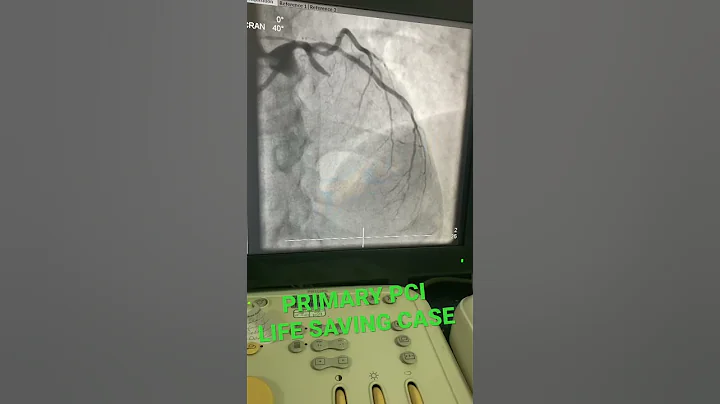

Primary PCI to LAD Patient presented with Acute Anterior Wall MI #Cardiology #MedEd #Foamed #USMLE #ACC #AHA ...